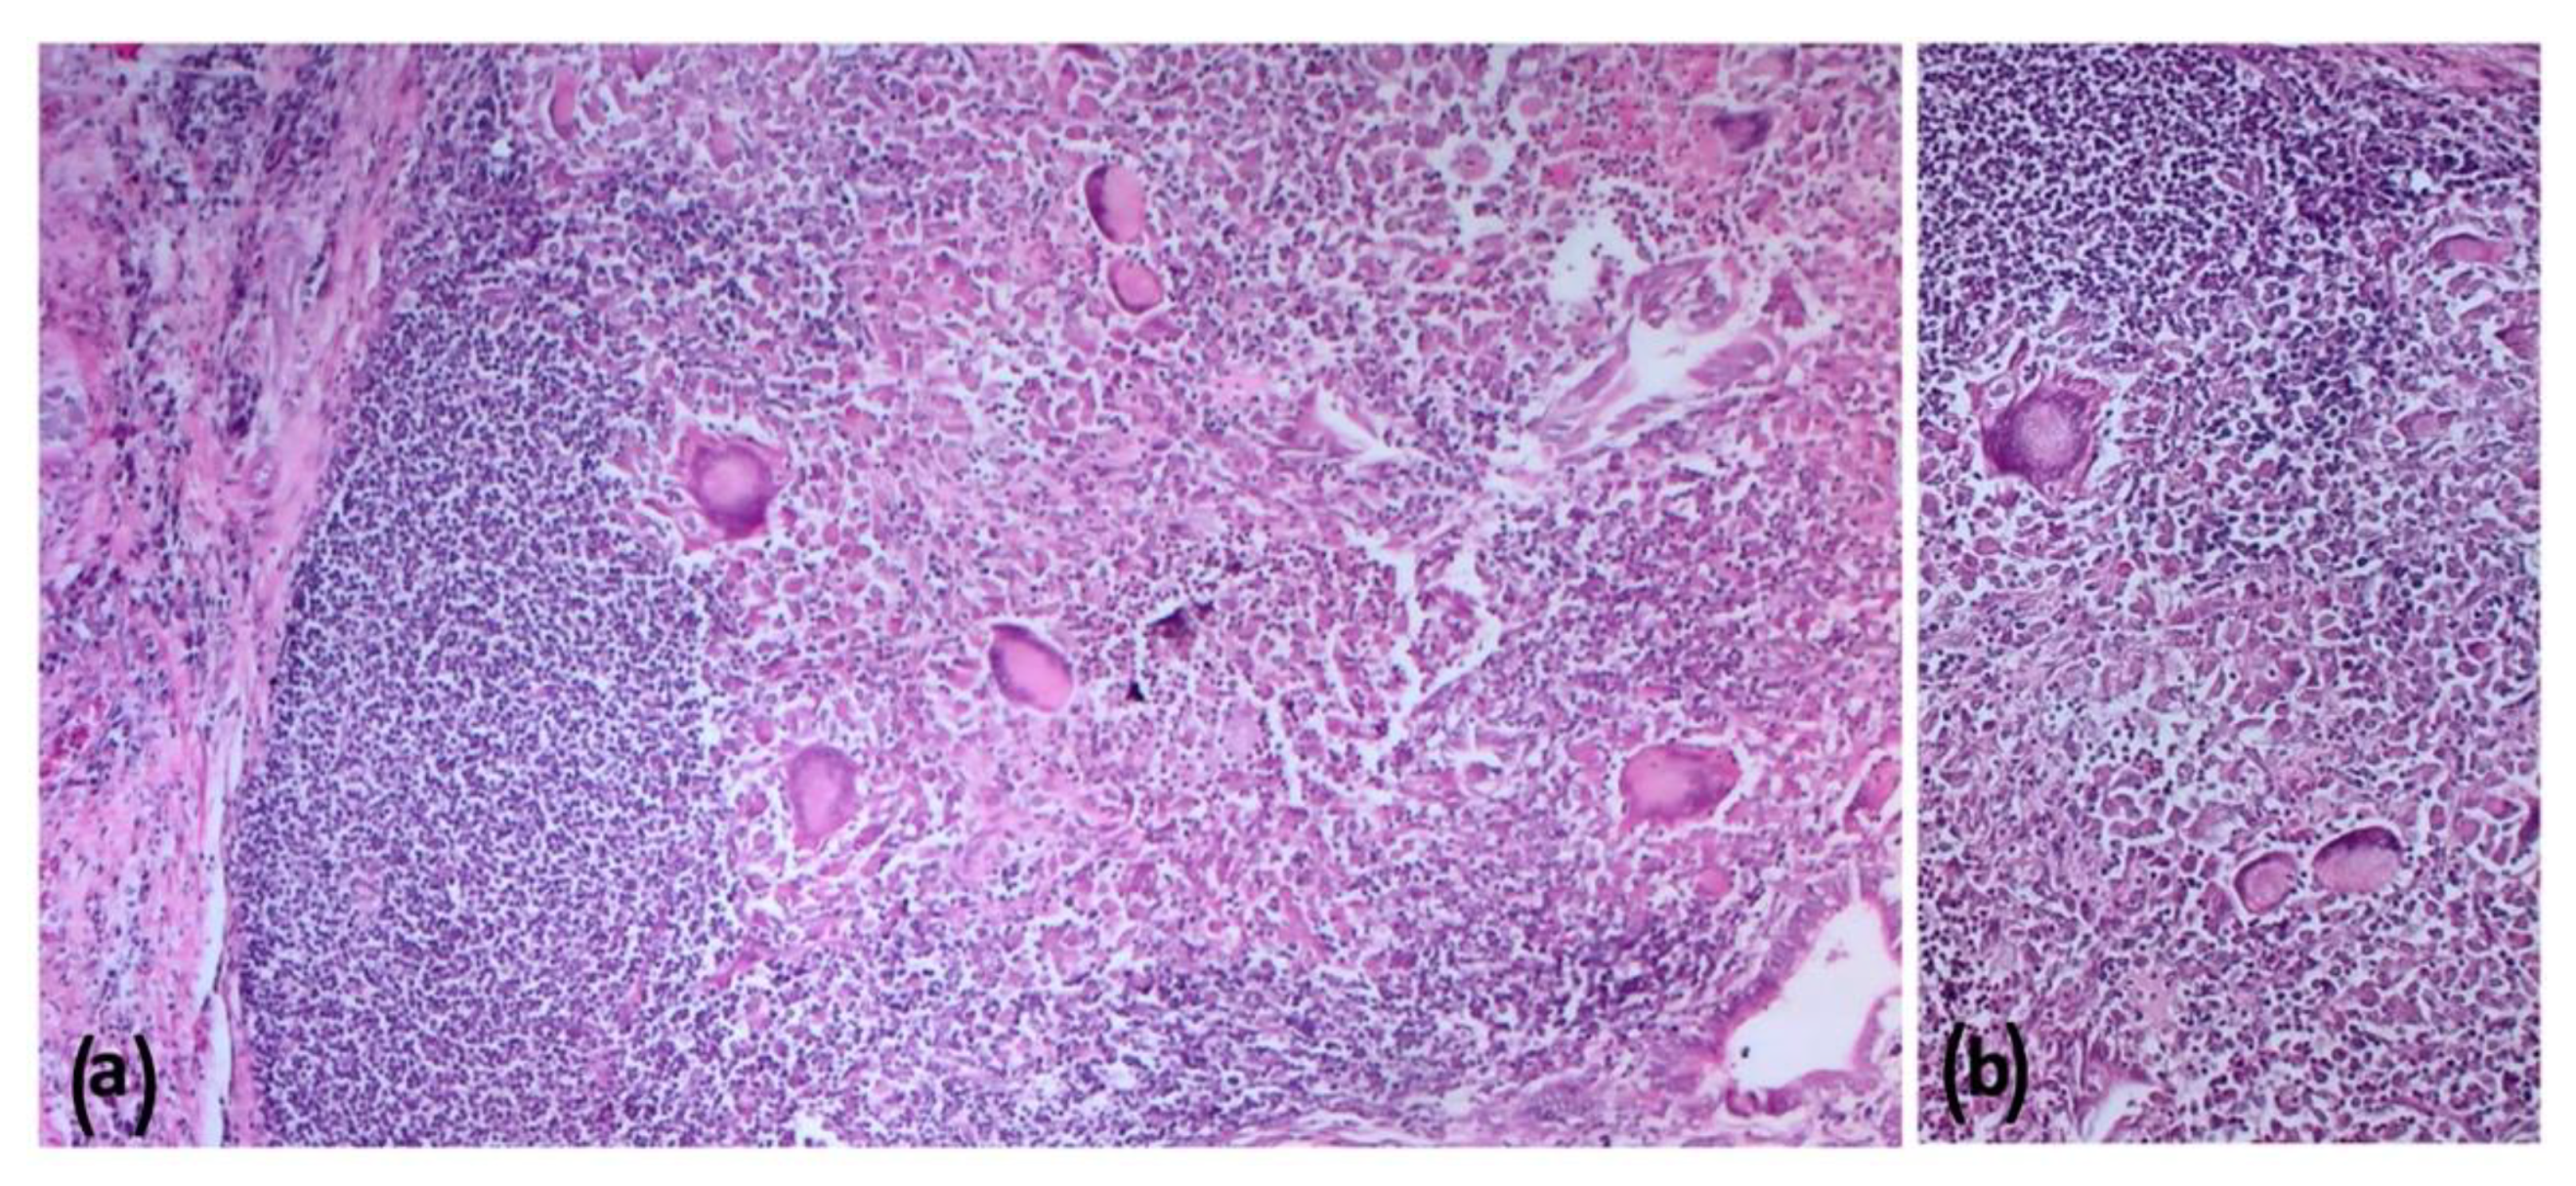

2.5. Histopathologic Findings